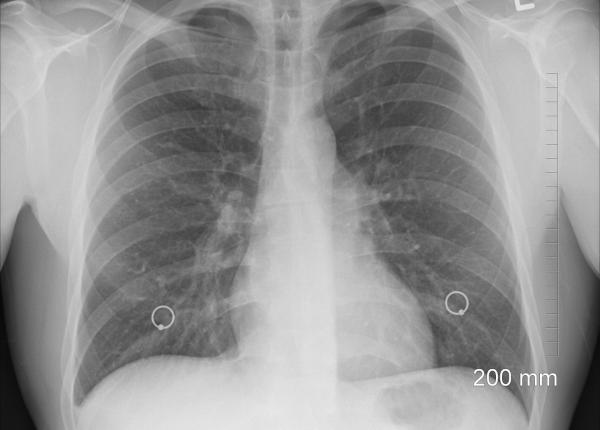

Cancer pulmonar: Lung Ambition Alliance, parteneriatul pentru creșterea ratei de supraviețuire

EXCLUSIV Dr Mădălina Grigoroiu, de ce nu scade numărul persoanelor cu cancer pulmonar. EXCLUSIV

ONG-uri: România are nevoie de un plan naţional de control al cancerului pulmonar

Țigările electronice: expunerea prelungită, risc crescut de cancer pulmonar

Un test de laborator efectuat pe șoareci a arătat că expunerea la fumul țigărilor electronice a determinat apariția cancerului pulmonar.